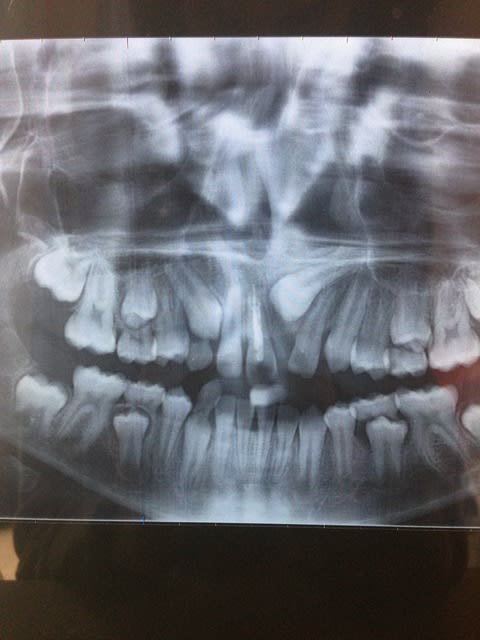

Cet enfant a 9 ans. A la suite d une chute a l école et d une panoramique nous découvrons que l incisive centrale 21 est incluse, retenue par un odontome.

L odontome a depuis été extrait pour faciliter l évolution de l incisive.

Nous avons réalisé l endo de 11 car elle s était nécrosée lors de la chute. Nous constatons depuis que la racine ne tiendra pas le choc puisqu on remarque un début de résorption apicale.

L incisive centrale 11 s est mésialée ainsi que l incisive latérale 22 fermant l espace d évolution de 21.

Je souhaiterai donc par des multi bagues reouvrir cet espace pour accueillir la 21 mais j ai peur en corrigeant l axe de 22 d entrer en contact avec 21 .

Et en distalant 12 et 11 vais-je fermer l espace d éruption de 13?

l incisive n est pas incluse mais retenue par l odontome qui a été extrait avant la pano... depuis elle commence à descendre mais manque de place

Il vous faut un CBCT sur ce cas.

Vous ne pouvez determiner les rapport des éléments dentaire ( surtout 21 avec la racine de 22 avec une seul panoramique. Vous pourriez prendre un cliché avec une incidence occlusal pour avoir plus d'information, mais les études on montré qu'avec la 3D sur ce genre de cas on change son plan de traitement dans 30% des cas par rapport a ce que l'on aurait fait avec la 2D seul.

Il y a débat en ce moment chez les ortho pour savoir quand on peut faire un CBCT et quand c'est du surtraitement. Ce genre de cas c'est la ou tout le monde est d'accord.

CBCT a faire

Une fois que vous aurez une vision 3D du problème la mécanique sera simple a choisir.

La 11 aurait nécessité un traitement d'apexification. Avec un apex si ouvert, le traitement endodontique risque de ne pas être stable à moyen/long terme.

Au vu du stade d'édification radiculaire de la 21, il te faudra probablement faire une désinclusion chirurgicale et une traction en plus de rouvrir l'espace.